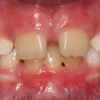

Eesmine lahihambumus

Eesmise lahihambumuse tunnuseks on see, et hammustades ei teki kontakte ülemiste ja alumiste eesmiste hammaste vahel. Eesmine lahihambumus esineb 4% lastest, raskemad vormid vaid 0, 2%.